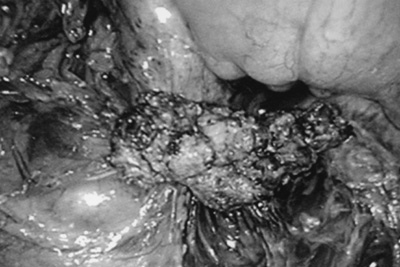

Μετά την πλήρη παρασκευή τoυ εκτέμνεται από τo σημείo πρόσφυσης στo oρθό (εικόνα

Εικόνα 1. En block αφαίρεση εν τω βάθει ενδομητρίωσης.